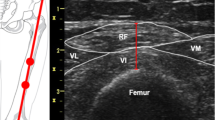

Quadriceps rectus femoris thickness (QRFT) and quadriceps vastus intermedius thickness (QVIT) were measured by B-mode ultrasonography, wall tracking ultrasound system (Philips hd7xe) with a 7.5 MHz linear array transducer (L12-3 transducer), as previously described in detail [15]. The right and left quadriceps values were assessed in both legs with the patient lying in a supine position with both knees extended but relaxed and toes pointing to the ceiling. A metric tape was used to identify and mark the two reference points in each leg. QRFT and QVIT were measured at the border between the upper third (RF,Prox; VI,Prox) and lower two-thirds (RF,Dist; VI,Dist) between the anterior superior iliac spine (ASIS) and the upper pole of the patella [15, 19]. The transducer was placed perpendicular to the long axis of the thigh with a large amount of gel and with no pressure to avoid compression of the muscle. The assessor was positioned on the side of the patient while performing the measurements, and was allowed to tilt the probe to obtain the best possible image, in which RF and VI would be aligned and centered. Measurements were performed directly on the ultrasound machine while obtaining the images. The vertical diameter of the muscles was measured at the widest point, on the inner edge of the muscle fascia. All thickness measurements are expressed in centimeters (Online resource 1). Ultrasound measurements were performed immediately before or not later than 12 h after CT scan (the median time lapse between US and CT scans measurements were 3 h after the CT). The US assessor was blinded to the CT scan results.

Online resource 1. Muscle thickness measured by ultrasound (in cm). QRFT, Quadriceps rectus femoris thickness; QVIT, Quadriceps vastus intermedius thickness. (TIFF 974 kb)